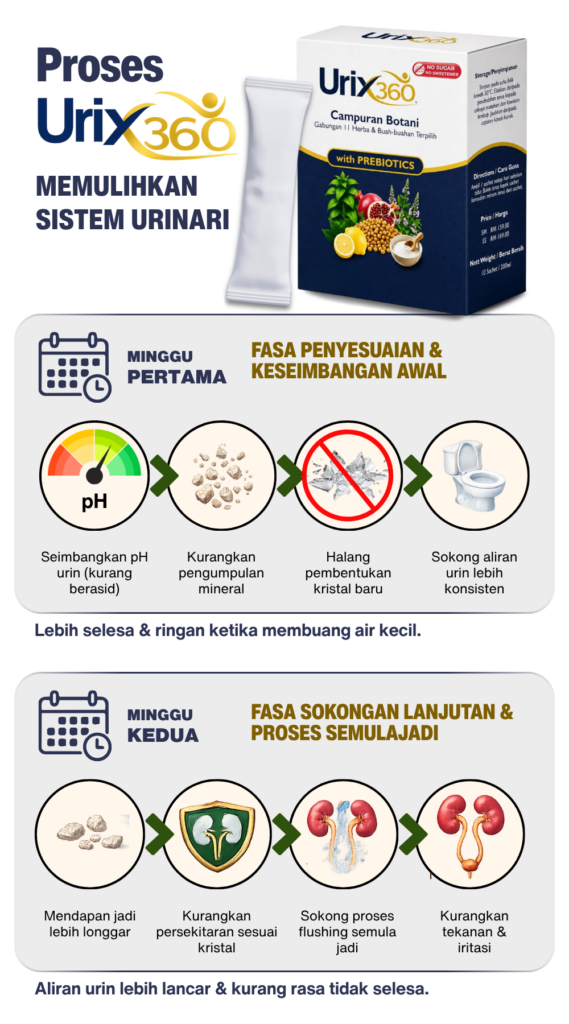

🔬 Bagaimana URIX360™ Membantu Sistem Urinari?

MELERAI TANPA BEBAN BUAH PINGGANG

Gambar Rajah Fungsi Urix360

ELAK TEKANAN PUNDI KENCING

Gambar Rajah Fungsi Urix360

SALUR LANCAR DAN PROSES PENYINGKIRAN 7X CEPAT

Gambar Rajah Fungsi Urix360